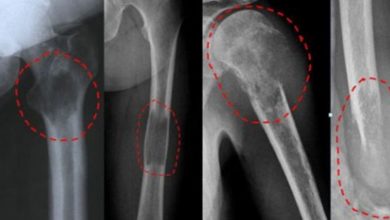

Basit kemik kisti

Nedir?: Kemiklerin içinde, İçi sıvı dolu, yavaş seyirli, genişleme özelliği gösteren kistlerdir. Daha çok çocukluk ve ergenlik döneminde görülür. Erkek çocuklarda…